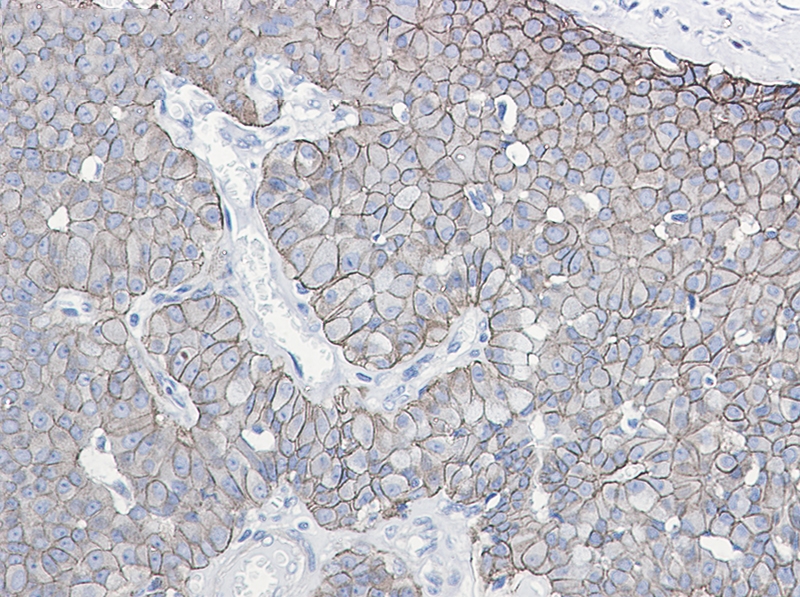

Immunohistochemistry of E Cadherin (phospho-Ser838/Ser840) in paraffin-embedded Human breast cancer tissue using E Cadherin (phospho-Ser838/Ser840) Rabbit mAb at dilution 1/50